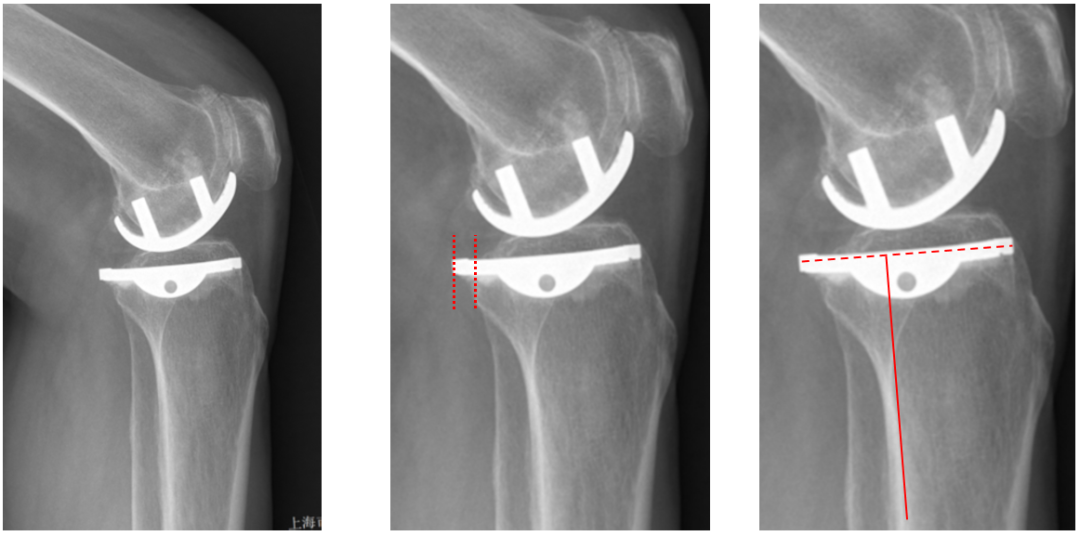

正位片标准胫骨和股骨假体位置

AP位假体位置:胫骨假体无内外翻,内侧缘超出胫骨平台内侧缘1mm; 股骨假体长轴与胫骨假体垂直,中线一致。

侧位片标准胫骨和股骨假体位置

侧位片假体位置:胫骨假体后倾3°,与胫骨平台前后缘齐平,股骨假体后倾40°,假体后缘与股骨后髁齐平。

胫骨假体厚度合适

胫骨垫片厚度合适:术前内翻畸形基本矫正,残留2-3°内翻。

股骨假体偏内放置,胫骨假体偏大

AP位胫骨与股骨假体位置:胫骨假体内侧悬挂>2mm,股骨假体中轴线与胫骨假体中线不一致,偏内侧。

股骨假体偏大且过度屈曲

侧位片假体位置:股骨假体后倾45°,假体后缘超出股骨后髁3mm, 胫骨假体后倾3°,与胫骨平台前后缘齐平。